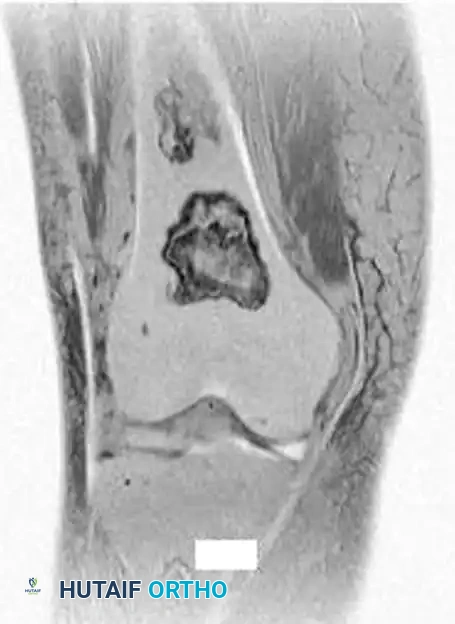

Fig. 20-22: (A and B) Pathological fracture of the right proximal tibia occurring through a large, expansile “brown tumor” of hyperparathyroidism in a 55-year-old woman.